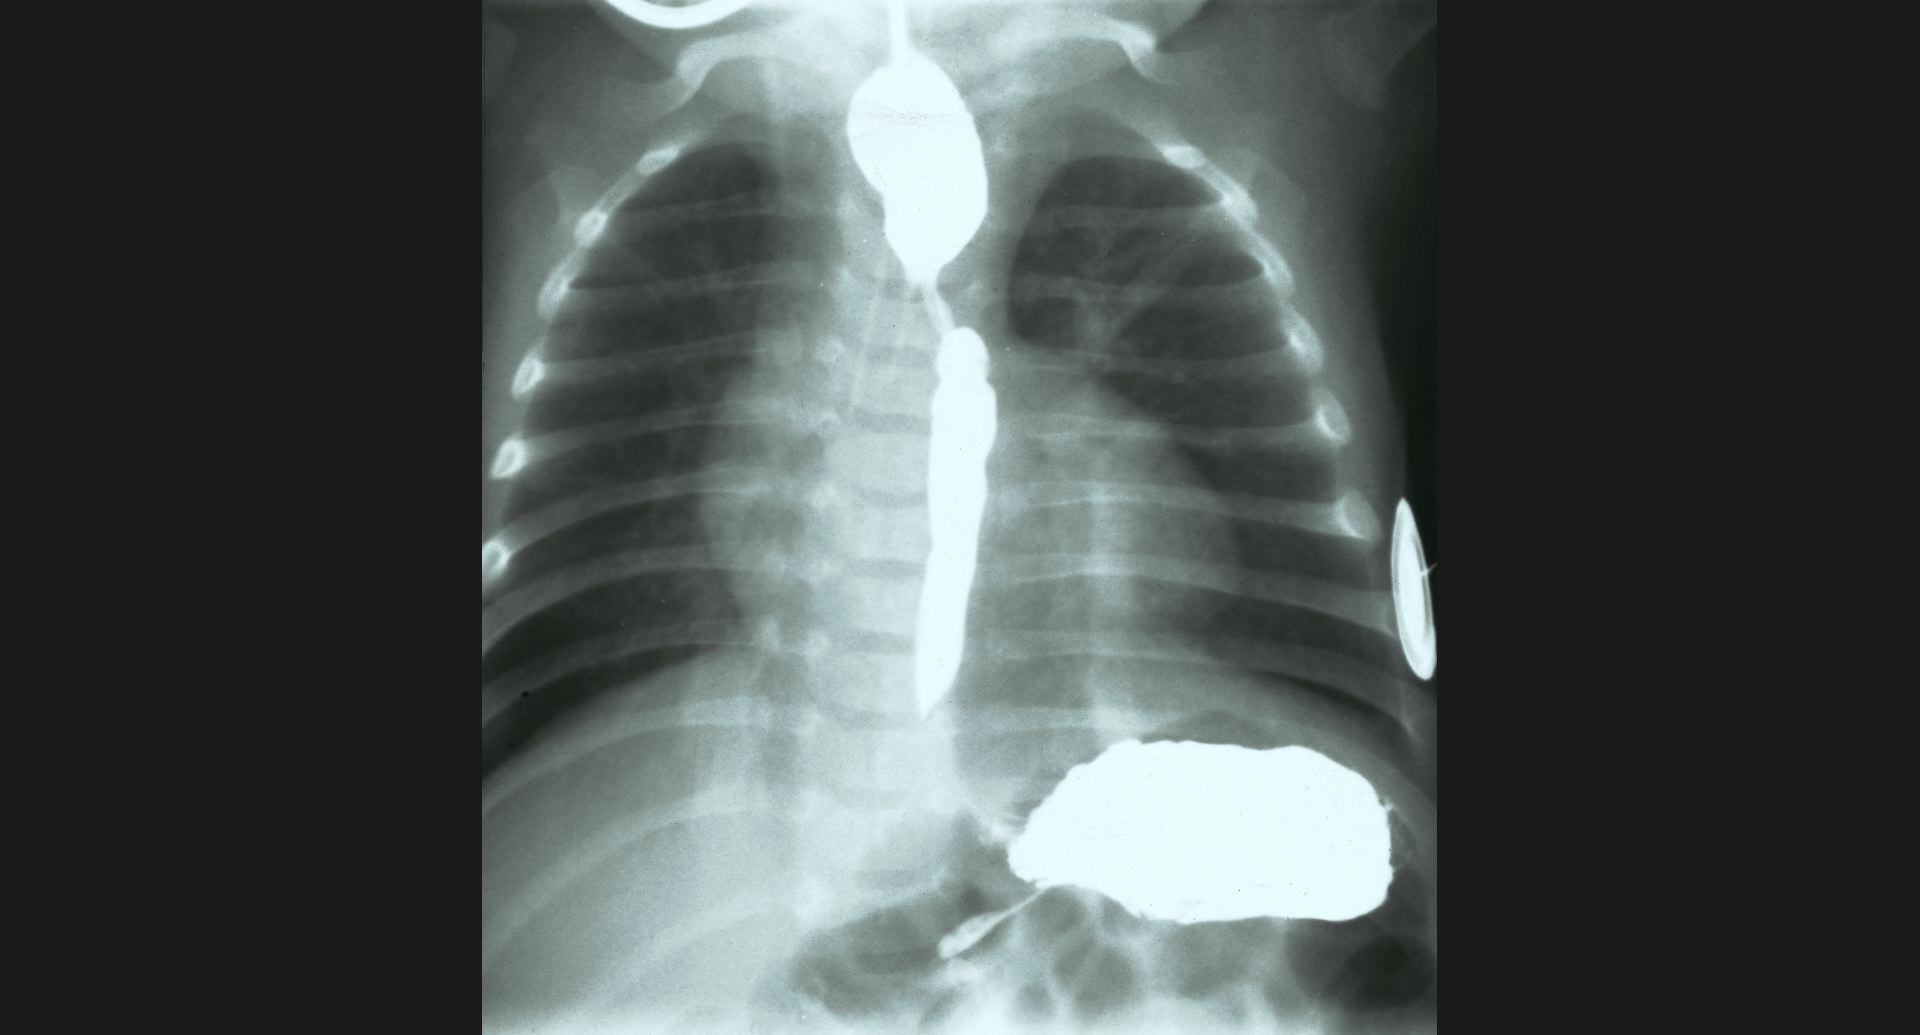

fig.4(104KB) :新生児の気管狭窄